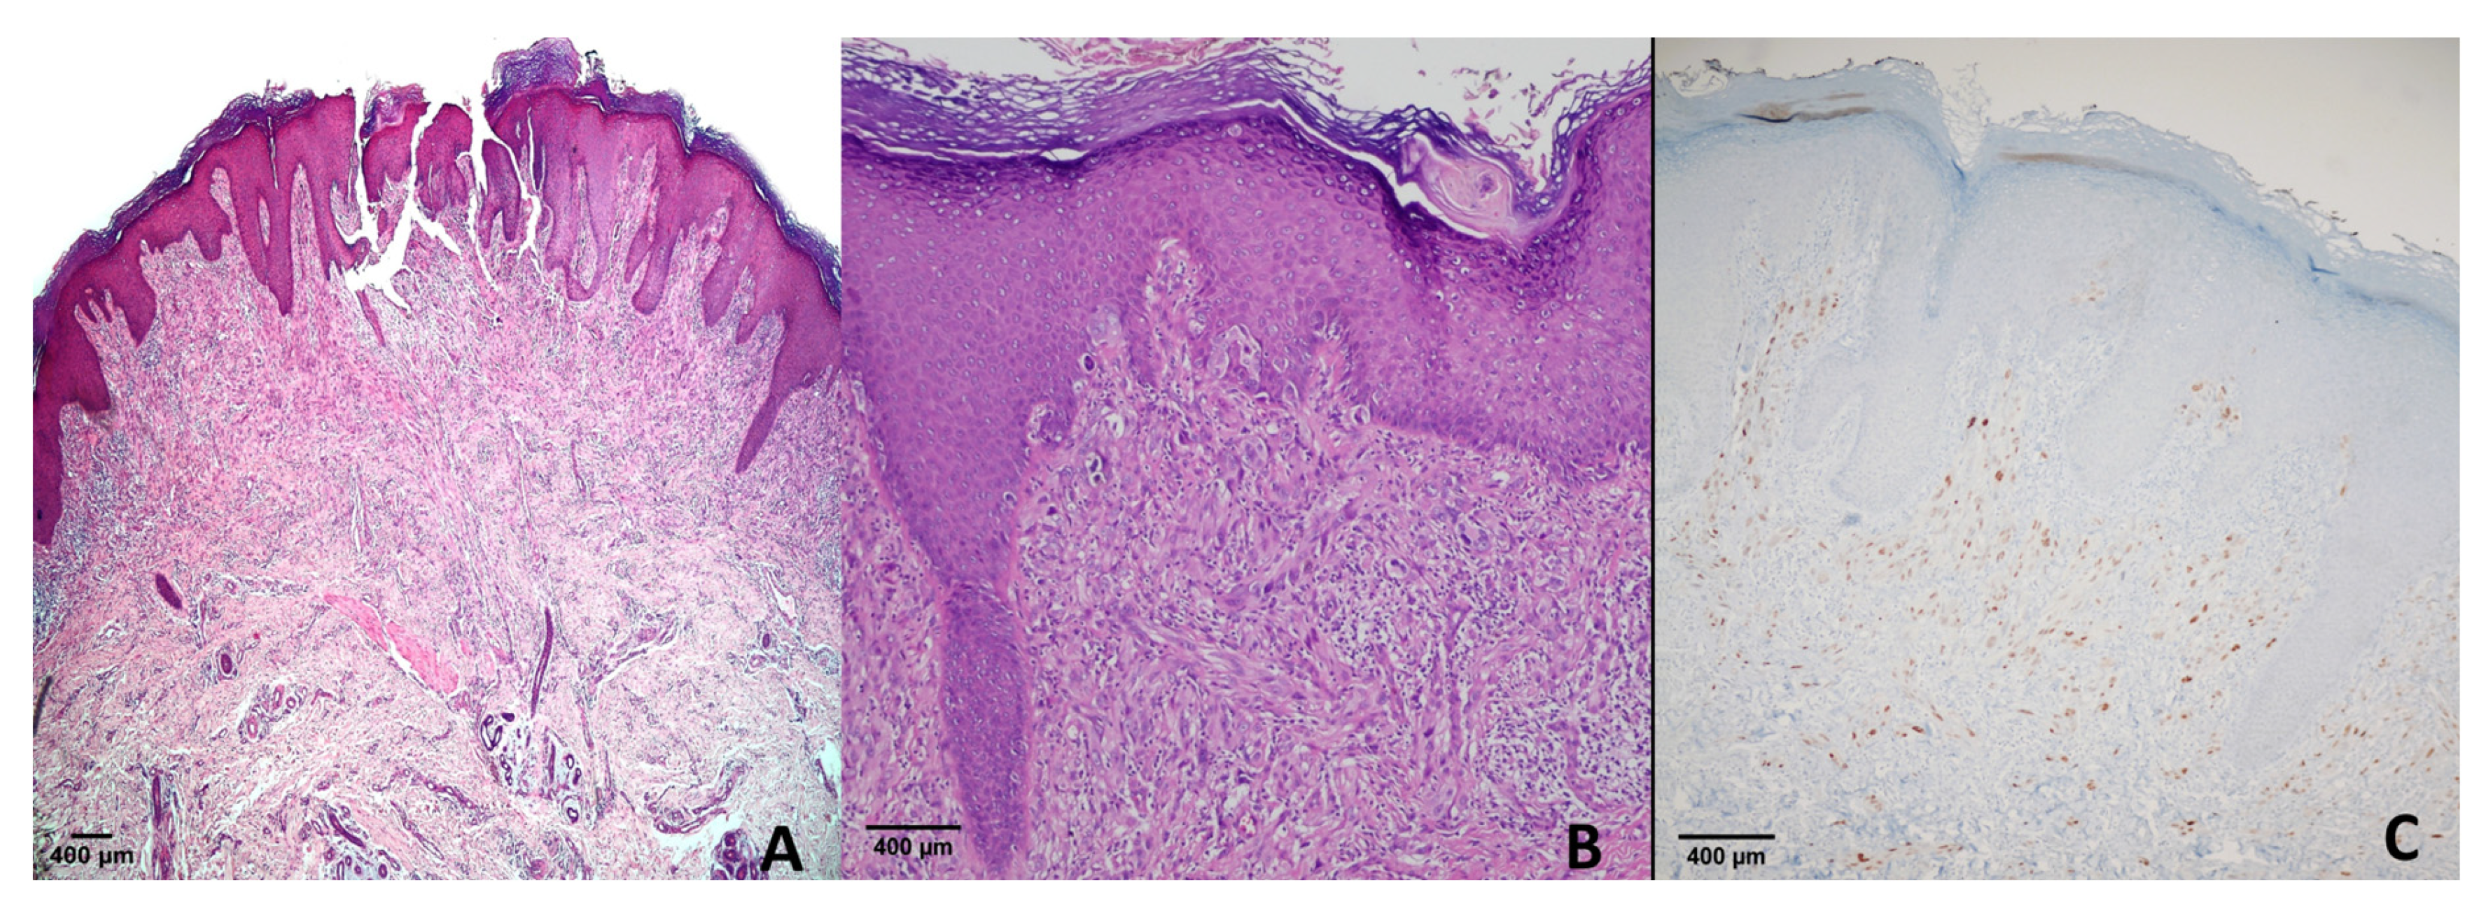

Mucosal Melanoma

Cutaneous Melanoma Subtypes